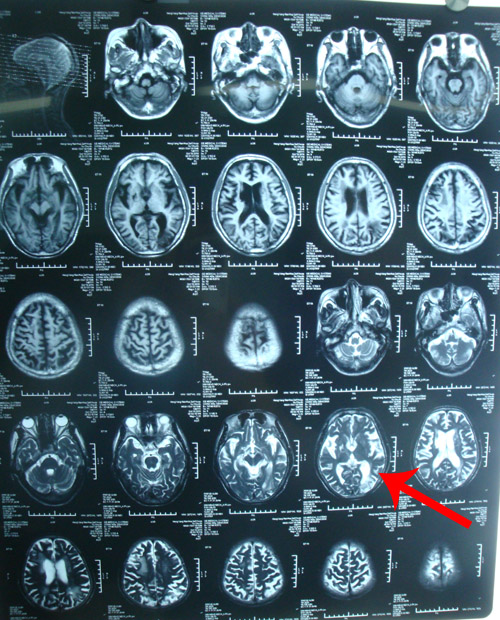

南华大学附一院头颅MRI示:左枕叶内异常信号,考虑脑梗塞可能性大。

颈椎MRI:颈椎退行性变,C3/4,C4/5,C5/6椎间盘向后突出。

该患者为老年男性,有高血压病史,以“后循环症状(反复头晕)”就诊,右侧基底节区陈旧性梗塞灶。造影及DSA检查证实其双侧颈动脉狭窄(右侧重),远端虹吸段亦存在狭窄;右椎动脉串珠样改变。因椎动脉呈串珠杨改变,无法进行手术操作。因此,建议通过手术取出颈动脉病变,改善脑部整体供血,既可避免中风发作,又可以通过侧枝循环改善后循环,缓解头晕症状。